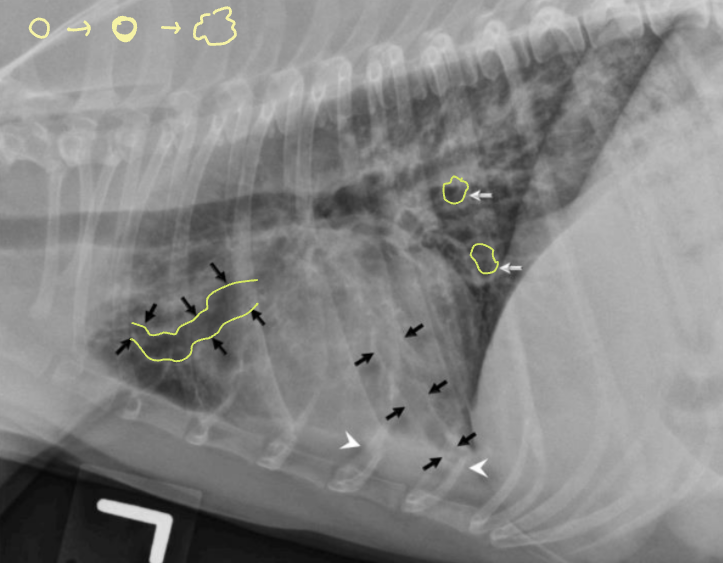

✳️ Bronchial pattern (기관지 패턴)

염증 세포 침윤으로 기관지벽 두꺼워짐

- Doughnut sign : end-on

- Tramline sing : side-on

원인

- Bronchitis (만성)

- Allergic (Feline asthma, 알러지성 폐렴)

- Immune-mediated (PIE)

주의

- 보인다고 해서 무조건 질병은 X

- 말단에서 다수 관찰되면 질병 가능성 ↑

✳️ ==Alveolar pattern==

Fluid, blood, cell 등이 균질하게 차 있음

* interstitial pattern에 비해 진하고 균질함.

- Consolidation (폐경화; 공기 외 다른 게 참)

- Lobar sign (엽과 엽 사이 경계가 드러남)

- Air bronchogram; “Trees in the fog” (폐엽이 차서 기관지가 드러남)

- Cardiac effacement

✳️ Interstitial pattern

벽이 두꺼워지고 공기가 차면서 지저분하게 나타나는 모양.

+ Nodular (구조성 간질 패턴) : 폐결절